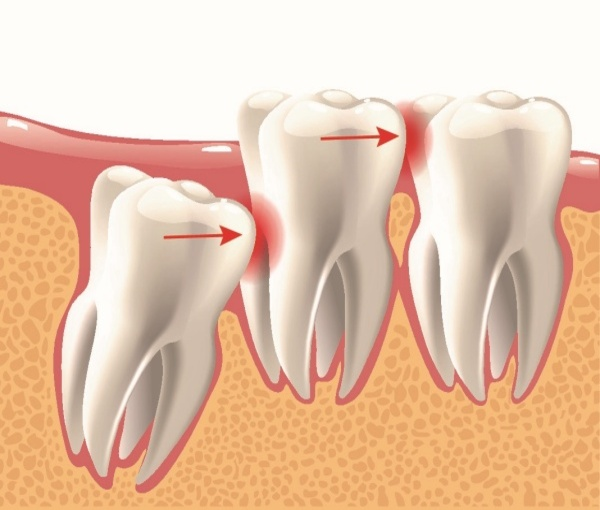

- Răng khôn mọc lệch hoặc mọc ngầm có thể đâm ngang, chèn ép răng số 7.

- Hậu quả: ê buốt, lung lay, tiêu xương quanh răng số 7.

- Trường hợp nặng có thể dẫn đến mất răng số 7 vĩnh viễn nếu không can thiệp kịp thời.

- Răng khôn mọc lệch có thể đẩy các răng phía trước ra khỏi vị trí, gây răng chen chúc, lệch lạc.

- Mọc lệch còn khiến khớp cắn hai hàm không cân đối, dẫn đến đau hàm, khó nhai và thay đổi hình dáng khuôn mặt.